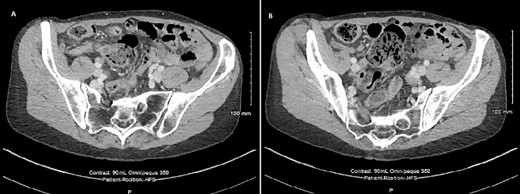

Radiological imaging for the thorax, abdomen, and pelvis was done to further characterise the lesion at the appendix and any other associated lesions. This showed a 10 mm low attenuation lesion at the base of the appendix (Fig. 2A). The upstream appendix was normal in diameter at 6 mm but mildly thickened wall containing a small volume of fluid (Fig. 2B). A 2 mm left lower lobe nodule was also seen with appearances similar to an intrapulmonary node.

CT scan of the abdomen showing (A) 10 mm low attenuation lesion at the base of appendix and (B) mildly thick walled appendix containing a small volume of fluid.